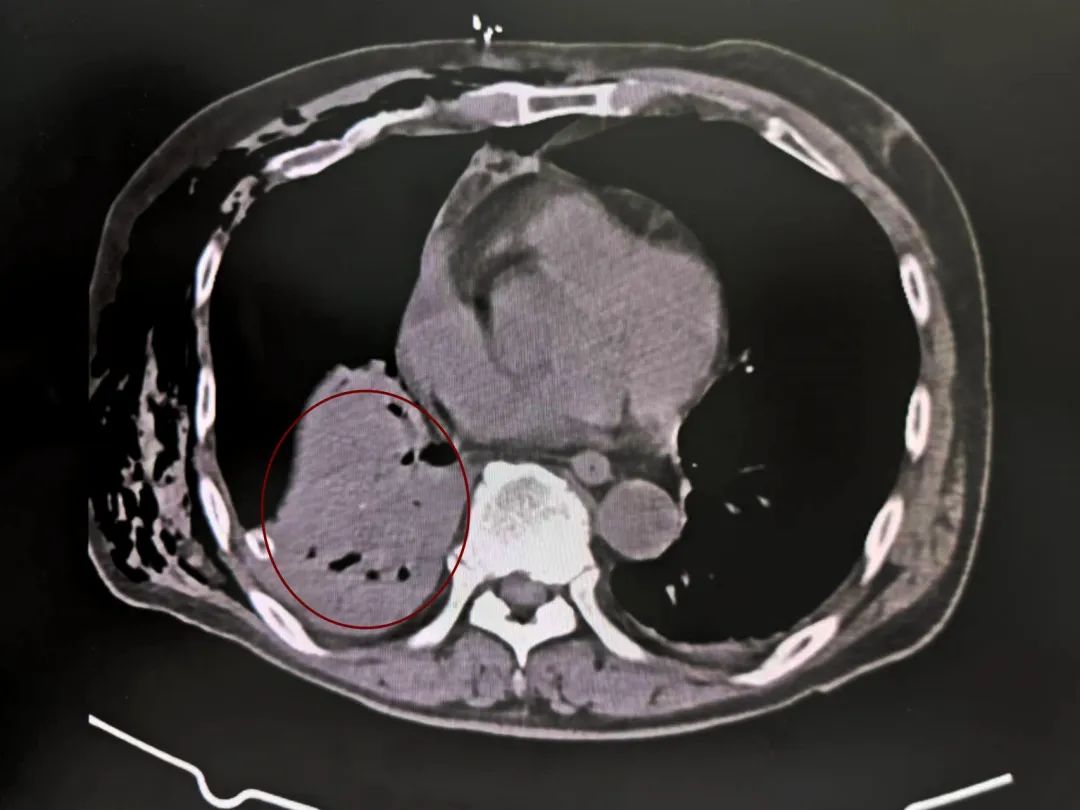

遭受严重创伤后,罗叔紧接着陷入昏迷。头皮血肿、血气胸、右胸腹部广泛的皮下气肿、血压持续降低等复杂危急症状接踵而至。这是一场与死神赛跑的硬仗,而留给和佳医院急救中心的时间以秒计数。

头部血肿

血气肿

多处骨折

皮下气肿

系统检查提示:罗叔目前存在车祸后多发伤,头部、胸部、腹部等存在多处外伤,颅脑的挫裂伤,右侧颌面部撕裂伤,右肘关节皮肤裂伤等全身多处皮肤擦伤。外表的伤口已经足够狰狞,而在罗叔的身体内部存在更严重的情况:闭合性颅脑损伤、呼吸衰竭、右侧6根肋骨骨折伴血气胸和皮下气肿、代谢性酸中毒、呼吸性碱中毒,还有肝、肺挫伤等脏器损伤。